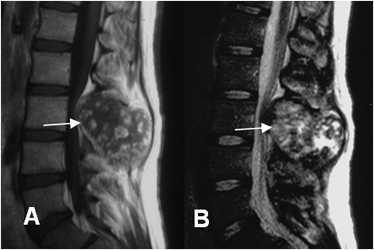

En la RM son hipointensos en T1 e hiperintensos en T2. Si la mineralización de la matriz es extensa, puede ser heterogéneo o hipointenso en T2. (13). (Fig 67 A).

En las vértebras predomina la lesión lítica, que puede producir expansión. En los casos agresivos hay ruptura de la cortical y masa de tejidos blandos. (16). (Fig 67 B).

Fig 67 A. Osteoblastoma.

A: RM sagital en T1 y B: RM sagital en T2. lesión expansiva que compromete los elementos posteriores vertebrales, heterogénea y de predominio hipointenso en T1 e hiperintenso en T2, por osteoblastoma.